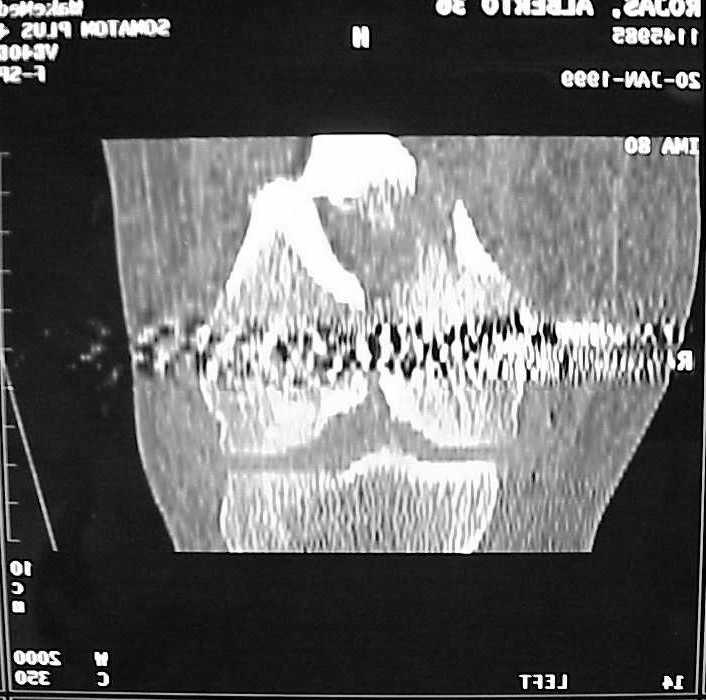

So I think a TAC of the knee could be useful.

A CT and knee xrays would help identify lateral condyle comminution and/or a "hoffa fragment" of the posterior condyle. I am concerned that the lateral cortex is not sufficient to give purchase for a retrograde IMN. blocking screws could improve this as a possibility. A long blade or LISS if avaible would be my secondary choices. Good luck. Any chance you can get these cases transferred earlier when it

See attached case that was done several years ago before LISS. He had comminuted trochlea and anterior blocking screws were used to prevent anterior IMN cut-out.

Мы пошли на операцию с планом попытаться сделать закрытый интрамедулярный, а не получится - сделать аппаратом. Посчитали, что получилось, хотя на еженедельной конференции ожидаются некоторые проблемы с объяснениями ;-)

Насчет стабильности для ранней нагрузки, конечно, сомнительно, но при таком повреждении ранняя нагрузка противопоказана в любом случае. Для ранних движений Должно хватить. Снимки в следующем сообщении.